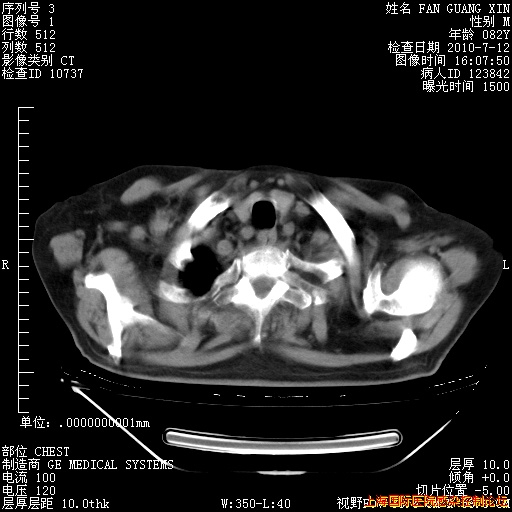

补发6月12日肺部CT肺窗

6月12日肺窗